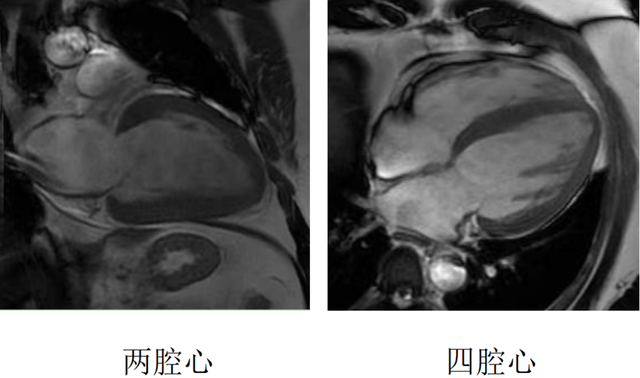

心脏磁共振被称为心脏“一站式”检查,通过多参数成像能够对心脏的结构、功能、室壁运动、心脏瓣膜、心肌灌注和活性进行“一站式”评估。主要通过电影序列(短轴、两腔心、四腔心、三腔心)、T2WI序列、首过灌注序列以及延迟强化序列对心脏进行综合成像。